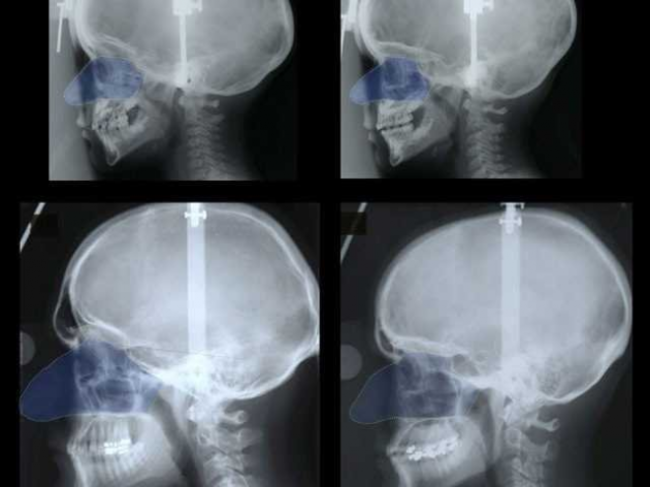

Top left: a boy’s skull and nose pre-puberty; top right: a girl’s skull and nose pre-puberty; bottom left: adult male skull and nose; bottom right: an adult female skull and nose.

The study, published last November in the Journal of Physical Anthropology, observed the facial changes of 38 individuals (20 males and 18 females) of European descent from age 3 to their mid-twenties.

Even at the same body size, researchers found that male noses grow disproportionately larger than female noses around age 11. (The researchers used sitting height and trunk-frame size — calculated as the product of sitting height and pelvic bone width — as their two measures of body size).